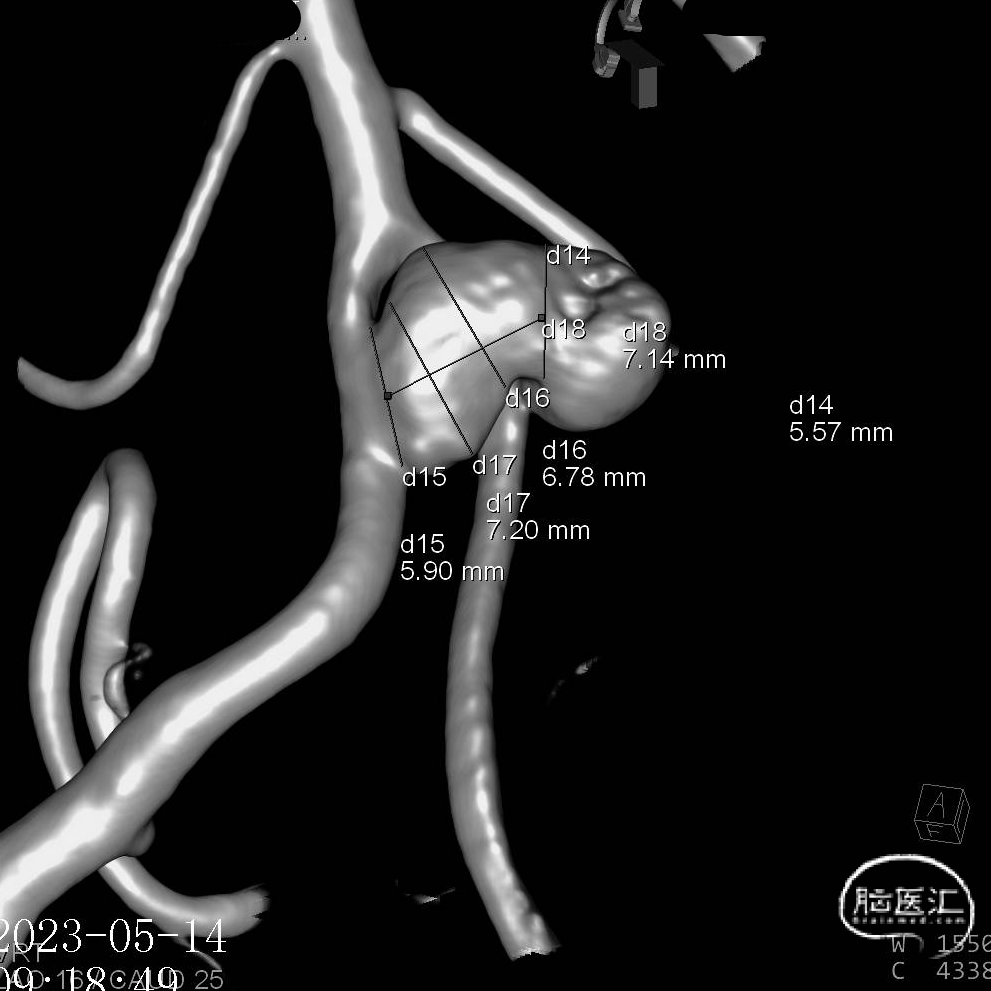

6.右侧颈内动脉C7段、左侧大脑中动脉M1段、基底动脉末端动脉瘤

动脉瘤一:基底动脉末端动脉瘤

(小脑上动脉瘤,侧壁)

动脉瘤一:基底动脉末端动脉瘤,由左侧大脑后动脉与左侧小脑上动脉瘤夹角处动脉瘤形成且为不规则状;瘤体上有子囊形成,左侧小脑上动脉从近心端瘤颈处动脉瘤瘤体上发出,动脉瘤与载瘤动脉近直角。

经测量可得动脉瘤宽度平均值为8.88mm,动脉瘤最小高度为7.71mm,瘤颈约为4.03mm。参考尺寸选择表,选择WEB™ SL 10*5,VIA™ 33微导管。